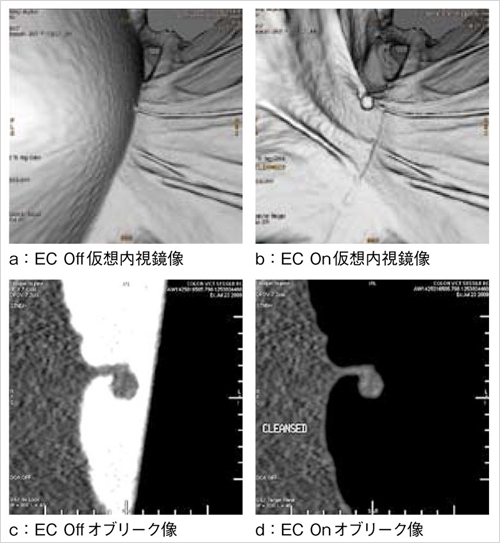

欧米では徐々に用いられるようになっている前処置として,前日の低残渣食と一緒に,少量のバリウムと検査直前にガストログラフインRを服用する方法がある2)。従来の前処置方法は,残渣・残液とポリープの境界が不明瞭であるため,体位変換を行い残渣・残液とポリープとの鑑別を行っていた。しかし,上記の前処置法を用いると残渣・残液のCT値が上昇するので,ポリープとの境界が明瞭になり,残渣や残液を自動でサブトラクションすることが可能である。従来の前処置法に比べ被検者の負担が少なく,術前の煩雑さも解消できる。Colon VCAR ECは,この自動サブトラクション機能(EC機能)を有する(図2)。まだ,わが国ではバリウムやガストログラフインRをどのように服用させるかが明確化していないため,この方法は一般的に普及はしていないが,EC機能は前処置の簡略化を大幅に進める技術である。

図2 Electronic Cleansing(EC)機能

従来の前処置法では,残液とポリープとの境界の不明瞭で体位変換をして残液を移動させて読影を行っていた。

本症例は,検査前にバリウムやガストログラフインRを服用し,残渣・残液のCT値を上昇させ除去を行った。